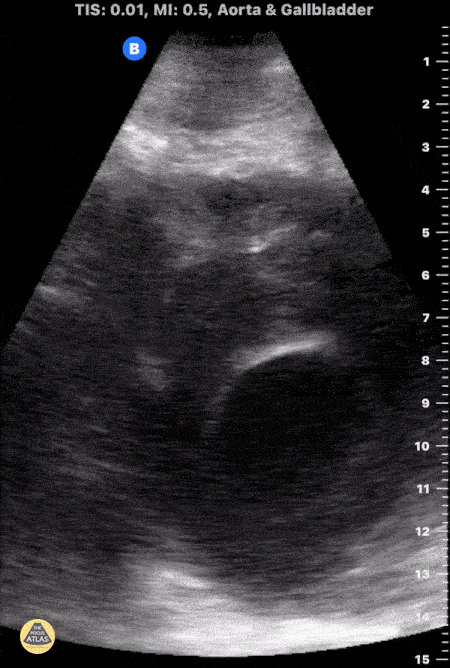

Aorta - Large AAA Rupture

This is a clip demonstrating a large abdominal aortic aneurysm with significant intramural thrombus. Signs of rupture can be appreciated near the right lower portion of the screen as there is disruption of the aorta wall. Heterogeneity within the intramural thrombus can also be an indicator of rupture. Michael Macias, MD